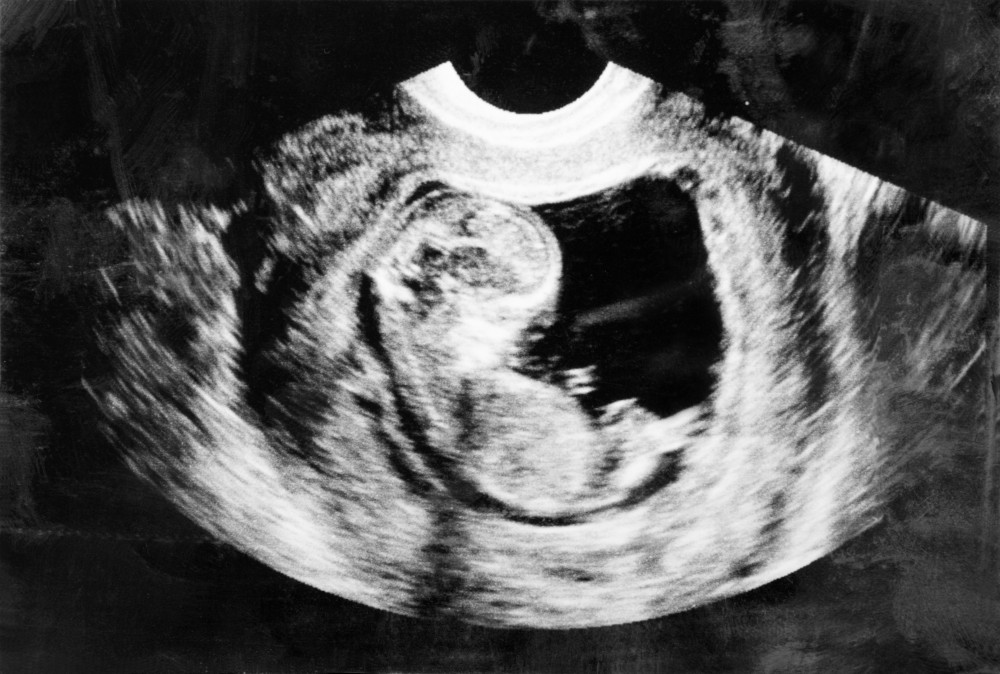

2.第一次照超聲波

聽心跳可能未夠形象化,但係照超聲波嘅時候,就確確實實見到BB嘅全貌。喺9至12周第一次照超聲波嘅媽媽,會見到一個小小嘅胎囊,裡面就有一個小巧又可愛嘅BB喇!雖然唔係好睇得明,但當醫生解釋畀媽媽聽BB嘅身體各部分嗰陣,媽媽真係可以感動到喊出嚟!